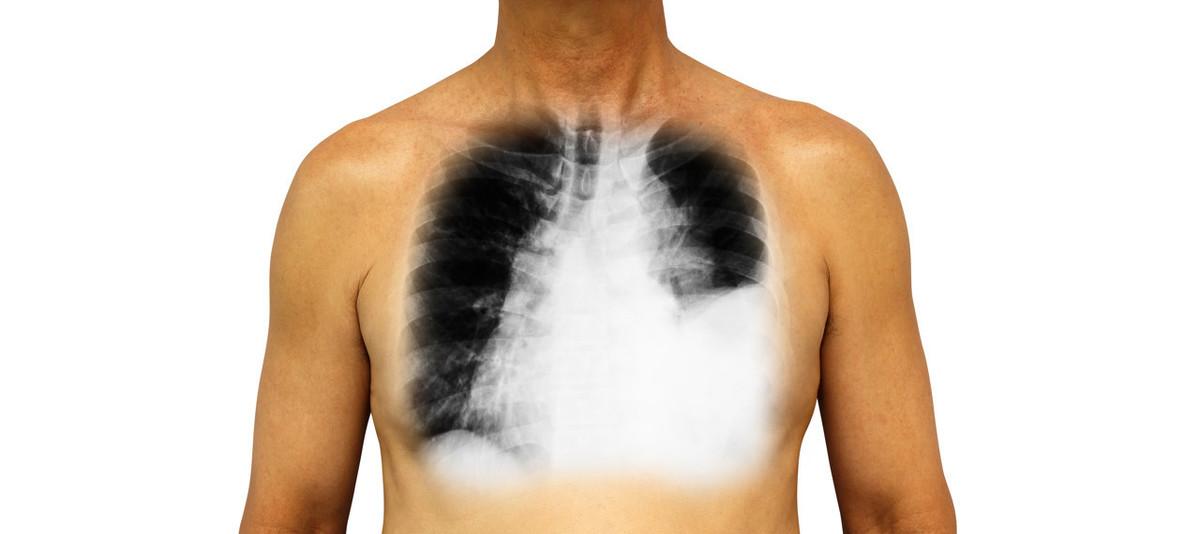

最近科里收治了一位年轻女性,40岁不到,不明原因莫名其妙的咳嗽胸闷气喘,当地检查胸部CT发现大量胸腔积液,左肺完全被压缩,整个胸腔看到的都是水一样密度的物质,得亏病人年轻,一般这样程度的胸腔积液放在年纪大的人身上早就气喘到只能躺在床上了,但这位病人已经适应了这样的胸水量,竟然只是咳嗽,并没有严重的气喘了。

当地也给抽了胸腔积液,查来查去都没有结果,一般来说这样的胸腔积液的量首先考虑结核,毕竟中国是结核大国,年轻人患有胸腔积液首先要考虑结核性胸膜炎的可能性,但胸水抽出来化验来化验去没有化验到结核菌,连胸水的性质也和结核性胸腔积液搭不上边,而且抽出来是血性胸水。